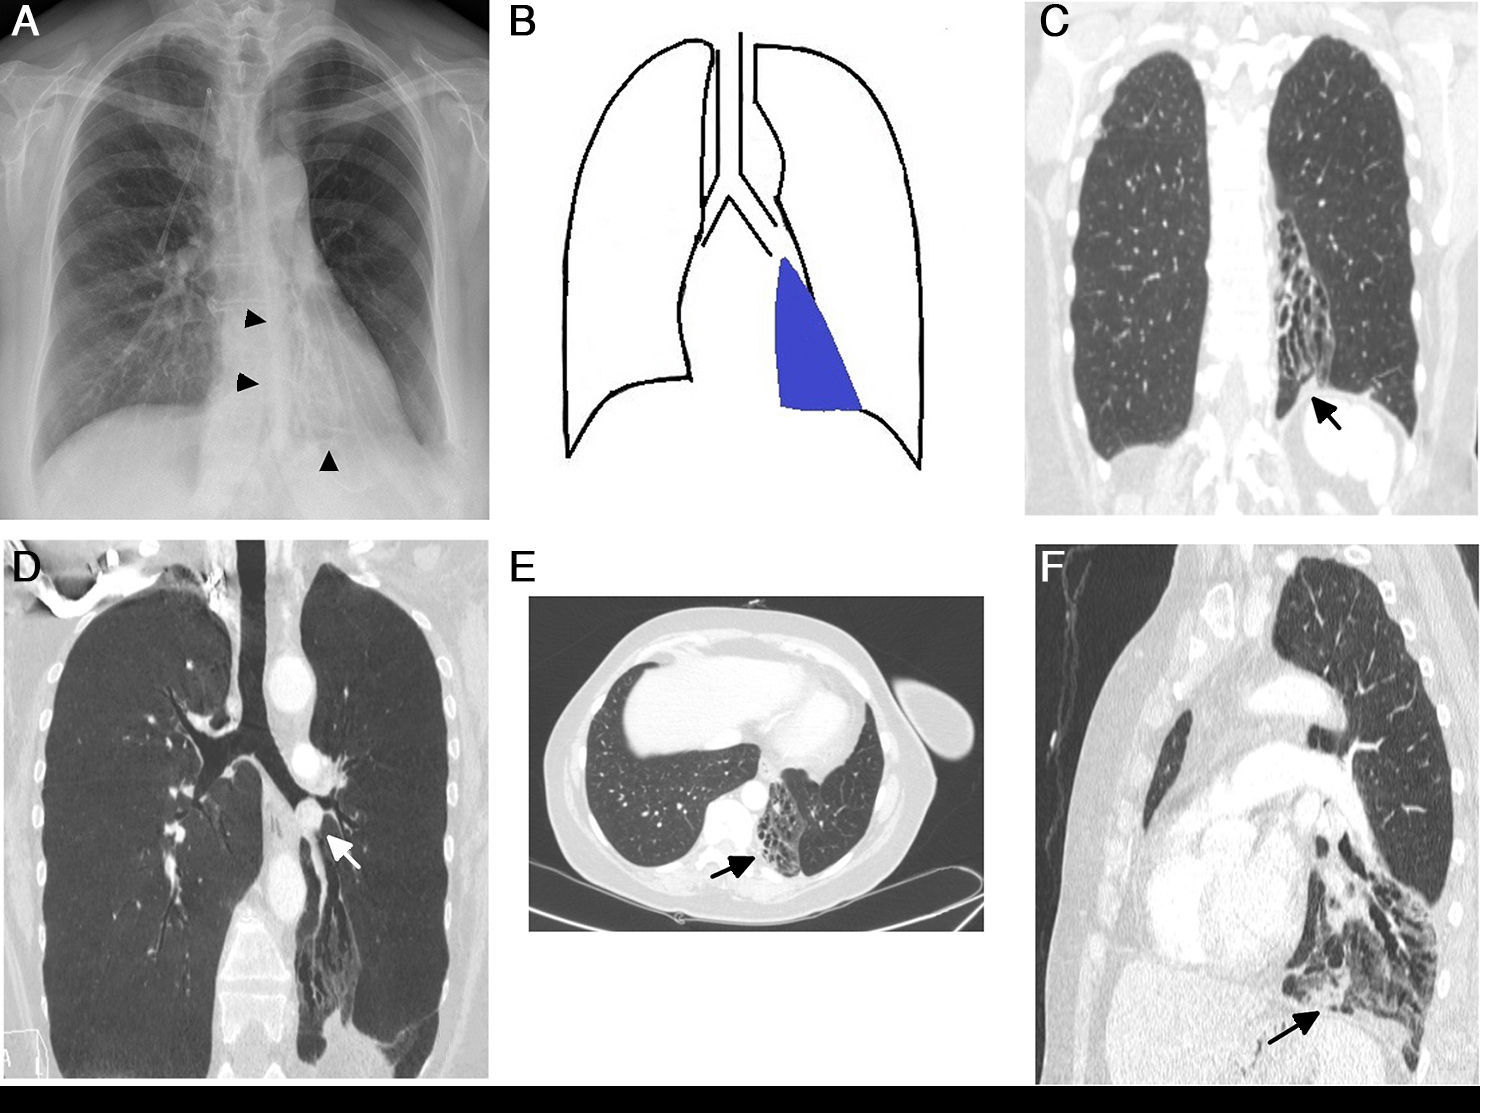

Atelectasis is an important indicator of potentially severe underlying disease that must be diagnosed as early as possible. One of the most common mechanisms is the reabsorption of air distal to respiratory tract obstruction. The chest X-ray is an excellent tool to diagnose atelectasis, and it is especially useful for ruling out central bronchial obstructions (e.g., from endobronchial tumors). If the signs of volume loss are not recognized correctly, the diagnosis and treatment can be delayed. This article describes the main findings of lobar atelectasis on chest X-rays and their correlations with CT findings, including the classic signs described in the literature and other, less known and sometimes subtle signs.